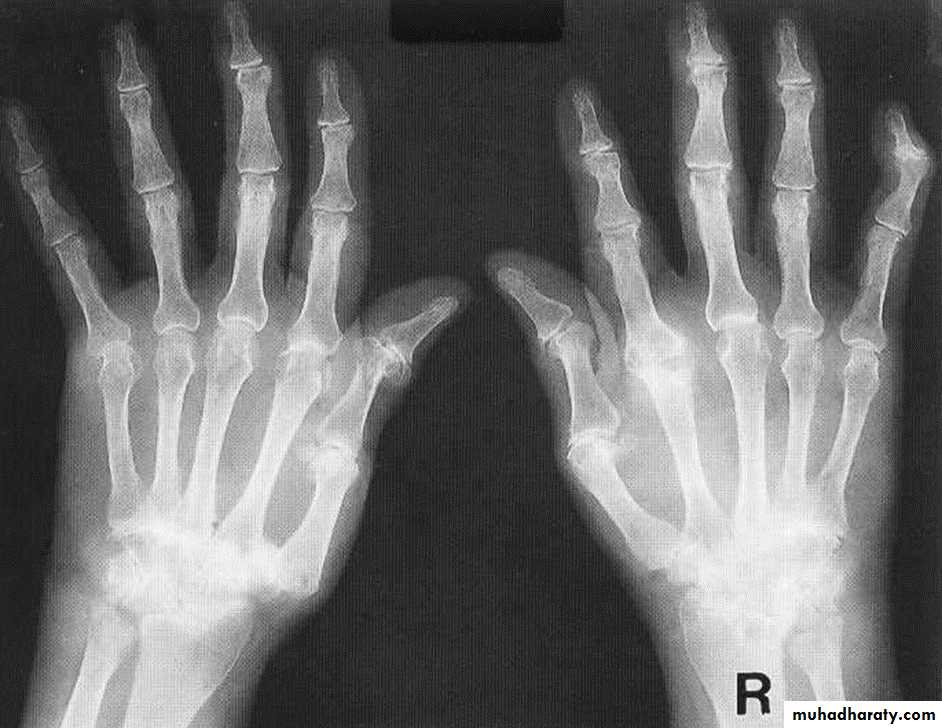

Rheumatoid arthritis. Bilateral changes are fairly symmetrical. Soft-tissue swelling is demonstrated, especially over the ulnar styloids. Erosions are demonstrated at the carpus, distal radius and ulna, with joint space narrowing and collapse of bone. Metacarpophalangeal erosions are also seen associated with joint space narrowing. There is a swan-neck deformity of the right fifth distal interphalangeal joint

Gross rheumatoid arthritis at the carpus with ulnar deviation,

subluxation and joint narrowing at the metacarpophalangeal joints.Boutonniere deformities are present at the index and little fingers.